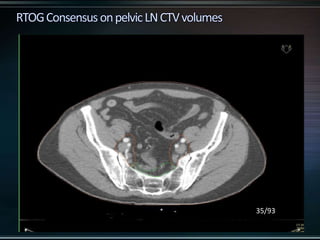

RTOG GU Consensus on pelvic LN CTV volumes:

 Commence contouring the pelvic CTV LN volumes at the L5/ S1

interspace (the level of the distal common iliac and proximal

presacral lymph nodes).

 Place a 7-mm margin around the iliac vessels connecting the

external and internal iliac contours on each slice, carving out

bowel, bladder, and bone.

 Contour presacral lymph nodes from S1 through S3, posterior

border being the anterior sacrum, and anterior border

approximately 10 mm anterior to the anterior sacral bone

carving out bowel, bladder, and bone.

 Stop external iliac CTV lymph node contours at the top of the

femoral heads (bony landmark for the inguinal ligament).

 Stop contours of the obturator CTV lymph nodes at the top of

the symphysis pubis.

33/93

35/93